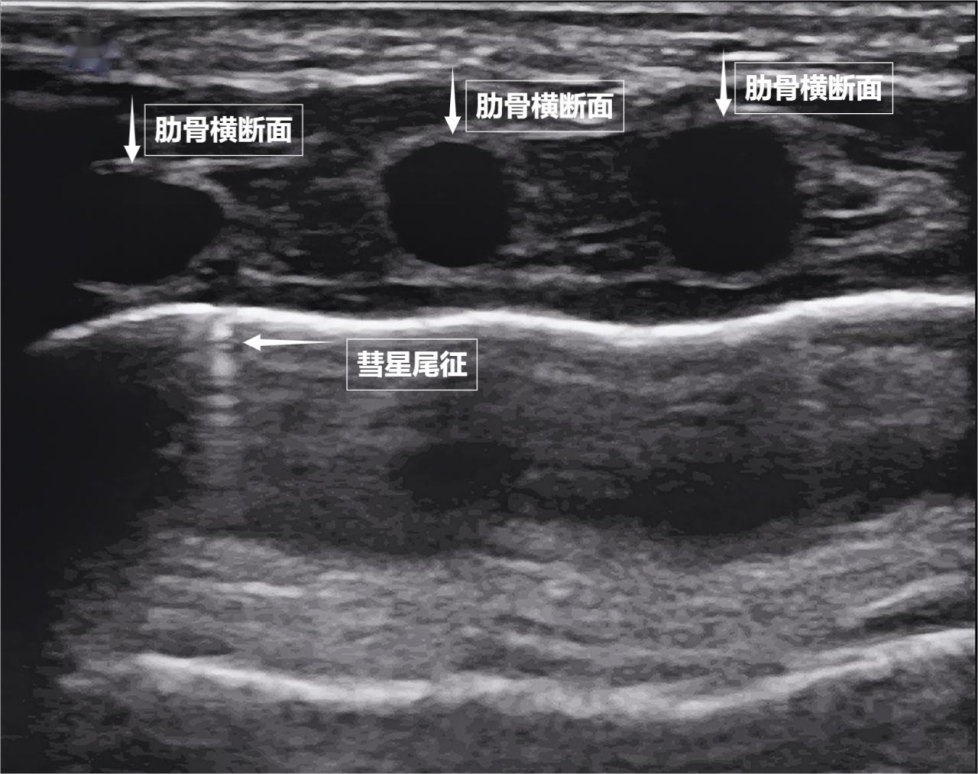

第二景:“沙滩与浪花”——肺滑动征如果我们把超声图像调成实时动态模式,把“照片”变成“电影”,更神奇的一幕出现了。随着呼吸,胸膜线会随胸廓运动轻柔滑动,这就是“肺滑动征”。它意味着肺与胸壁正紧密相依、自由顺畅地呼吸。若肺与胸壁间有气胸或胸腔积液,这种滑动会消失。有时,在胸膜线下方还会出现细小的亮白色闪烁点,称为“彗星尾征”(见下图)。其少量、孤立出现时,通常是正常肺小叶间隔的反射,无需担心。

图为正常新生儿肺部超声表现